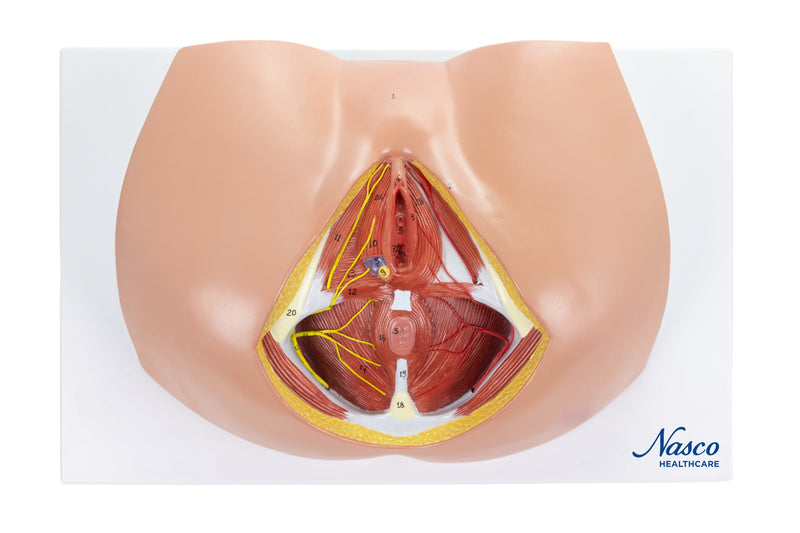

Female Perineum Model

A life-size model showing the female perineum area, including the anus and external genitals. The pelvic diaphragm, urogenital perineum with the opening of the vagina, and anal perineum are well represented. Distribution of blood vessels and nerve endings are included. Accompanying an interactive 3D anatomical model with augmented reality is a great tool to encourage learning and support. This platform allows students to engage in comparative analysis of anatomical models as they compare and contrast the structure of individual organs. This initiative also provides a platform for continuing education, providing opportunities for all students to increase their knowledge of anatomy, physiology and pathophysiology.

One-Year Warranty

Ship Weight (LBs): 3.7 lbs.

Dimensions. (Inches): 16.14 x 10.63 x 8.66